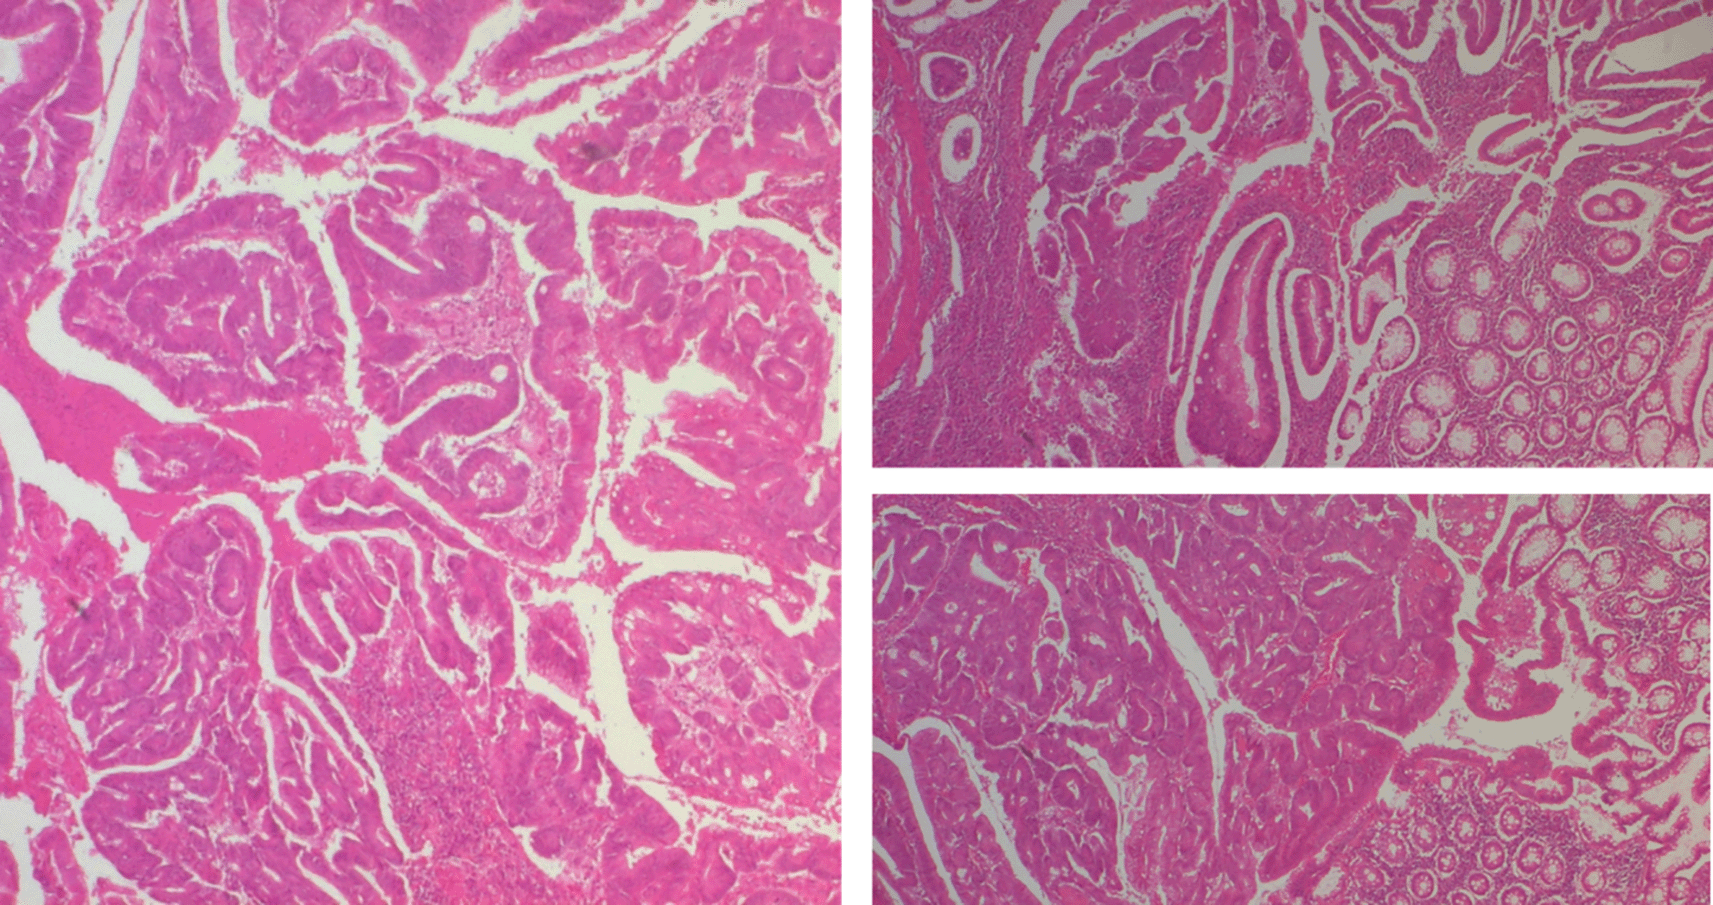

Regarding histology, the main tumor was a mixed gastrointestinal stromal tumor (GIST), with spindle cells in the submucosa and epithelial cells in the outer layers of the colonic wall, with a high risk of recurrence due to the innumerable mitoses, which exceeded 100 mitoses per 50 fields at high magnification, and the capsular rupture, according to the Miettinen and Joensuu classification ( Figure 5) and was classified pT4 according to TNM 2017 in the eighth edition.3

The polypoid lesion was an adenocarcinoma NOS type well differentiated developed on degenerated adenoma stadified pT1N0 (Figure 6).